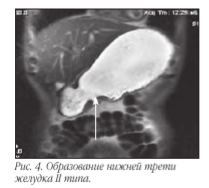

В связи с тем, что визуализировать достоверно все слои стенки желудка чаще всего не представляется возможным, то критериями ее поражения являются степень утолщения и протяженности изменений. При поражении всех слоев и распространении процесса за пределы серозы основными МР-признаками следует считать нечеткость и размытость наружного контура стенки желудка, снижение сигнала от перигастральной жировой клетчатки. В современной лучевой диагностике МРТ применяется для определения стадии по N и M стадиям, используя TNM классификацию. Мы в своей работе используем классификацию Японской ассоциации по раку желудка. В основе классификации JGCA (1998) лежит анатомический принцип. В отличие от принципов JGCA, классификация UICC (Международного противоракового Союза 2002) рассматривает лишь количественное поражение регионарных лимфатических узлов вне зависимости от их локализации.

Метастатическое поражение лимфоузлов, печени и брюшины - N, H и P.Основными признаками поражения стенок желудка являются: утолщение стенки более 5 мм, неровность и бугристость контуров, изменение МР-сигнала от образования, распространение за пределы стенки.